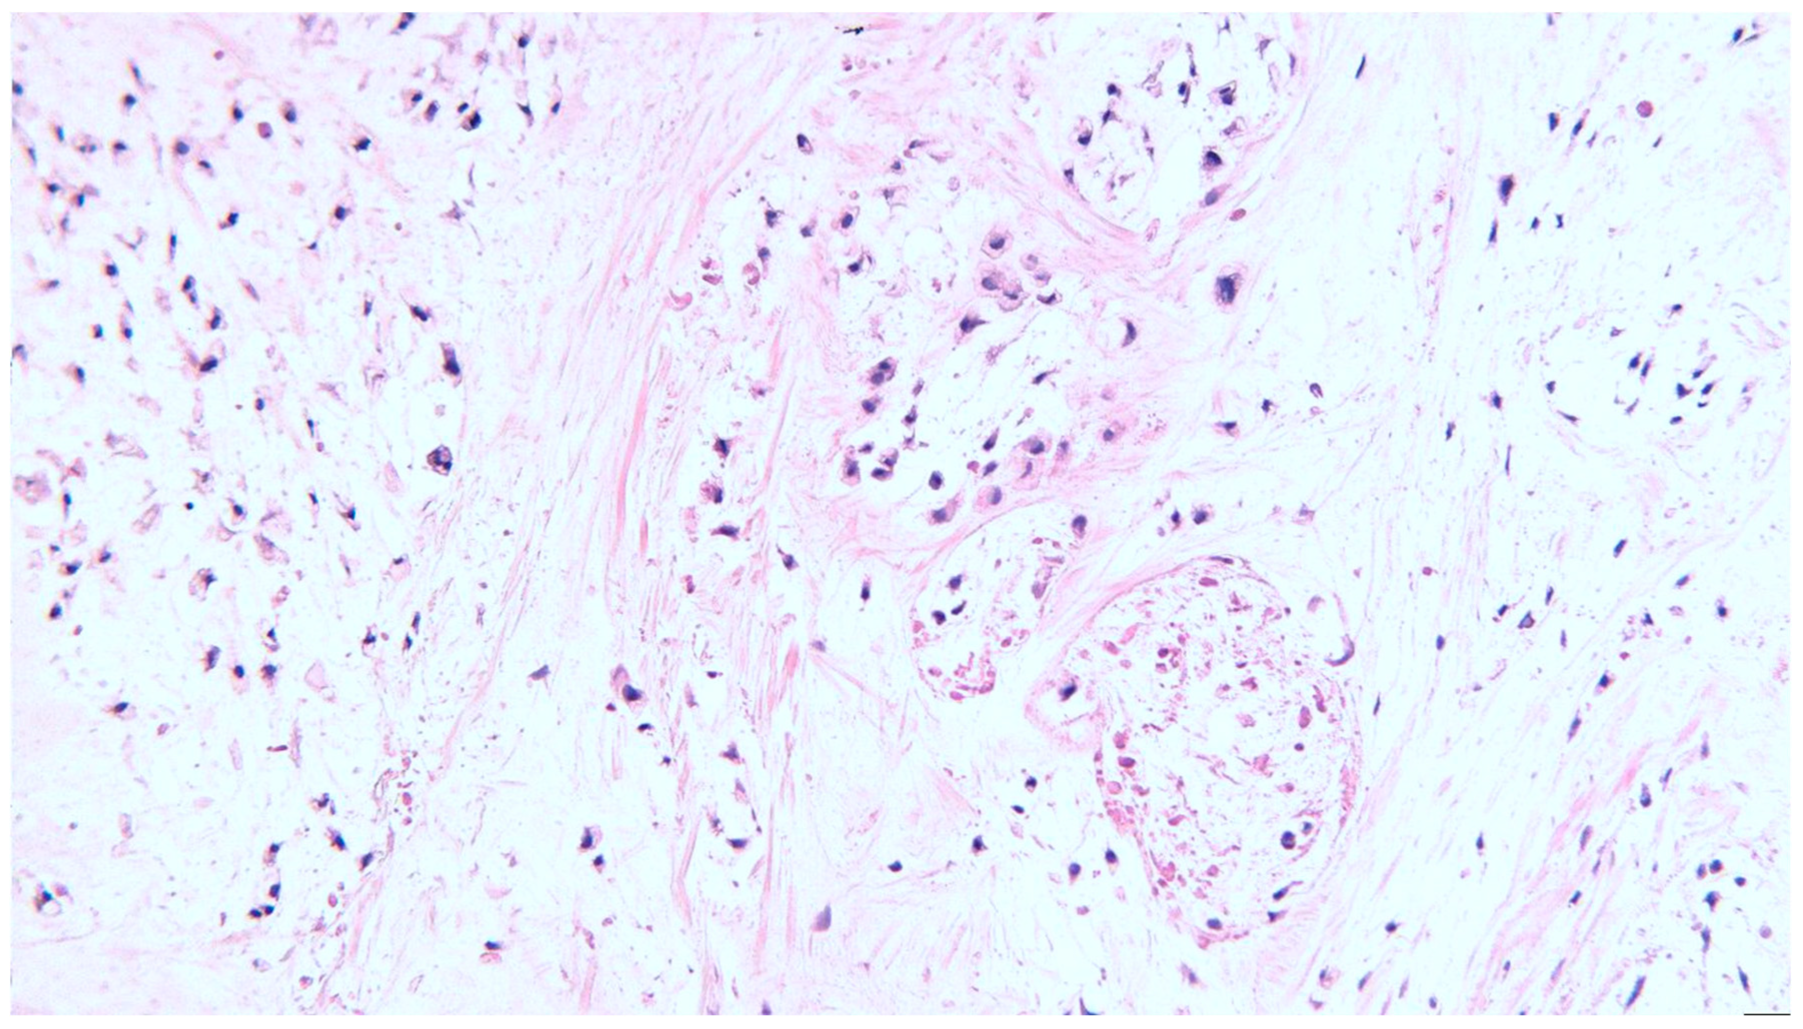

2. Clinical Case